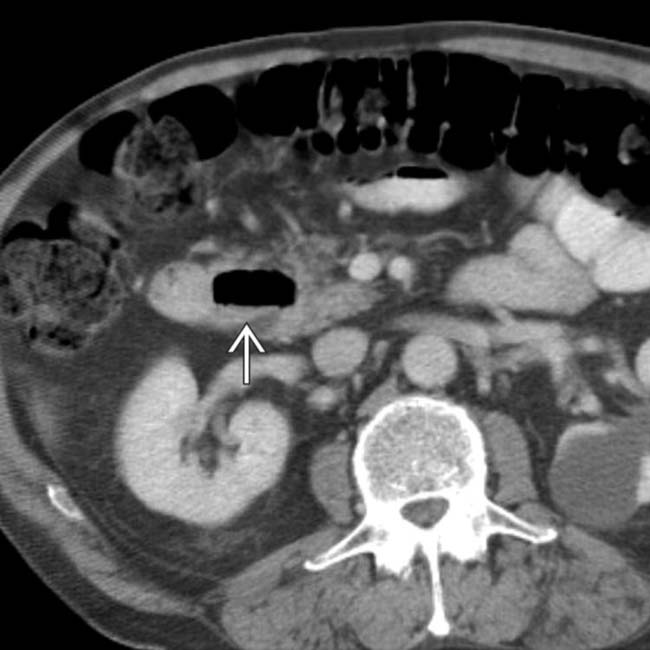

SMA Syndrome with Nutcracker Syndrome Vascular Case Studies CTisus

From ctisus.com

SMA Syndrome with Nutcracker Syndrome Vascular Case Studies CTisus Nutcracker Syndrome Duodenum The duodenum and the left renal vein (lrv) occupy the vascular angle made by the superior mesenteric artery (sma) and the aorta. Superior mesenteric artery syndrome is the compression of the third portion of the duodenum between the superior mesenteric. The optimal treatment includes open decompression of the left renal vein with renal vein transposition or gonadal vein transposition,. Superior. Nutcracker Syndrome Duodenum.